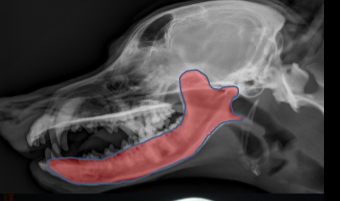

ID.

Mandible

ID Radiographic View

Lateral

ID

Maxilla

Zygomatic Bone

Orbital Margin

Coronoid Process of Mandible